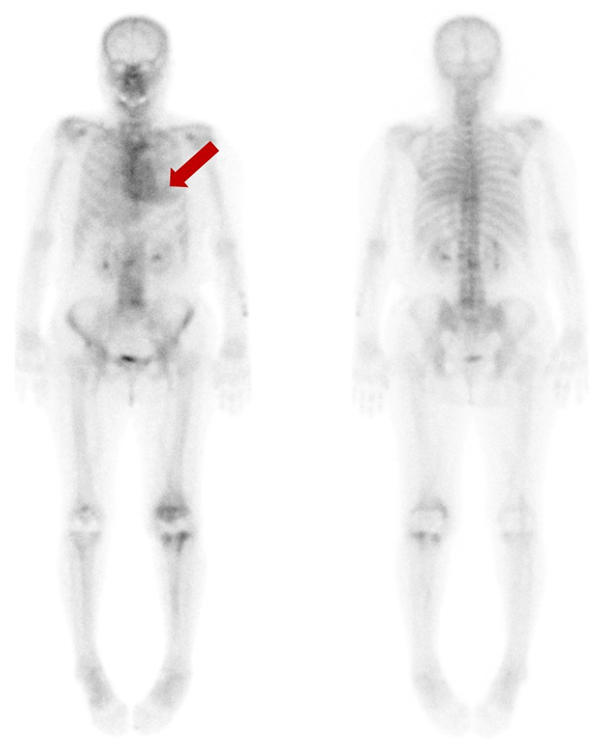

Figure 1.